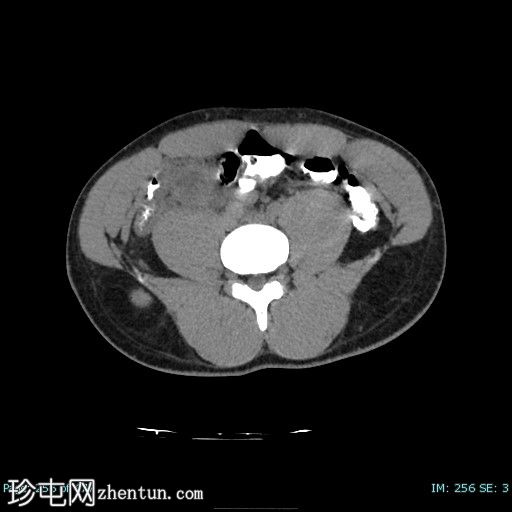

1.jpg

轴位

平扫

阑尾壁增厚并强化。

阑尾与一个厚壁强化脓肿相连,脓肿大小约3.2 x 4.3 cm(横径 x 纵径),内含气体。

周围肠系膜淋巴结肿大,脂肪浸润,并可见积液。

盲肠极炎症性增厚。